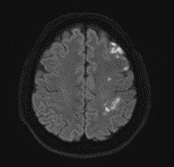

그림18.png

<Fig 1. 좌측 급성 뇌경색으로 진단된 뇌 mri 검사>

그런데 MRI 결과를 보는 순간...

심장이 덜컥 내려앉는 기분이었습니다.

좌측 대뇌에 급성 뇌경색 소견이 보였습니다.

그것도 꽤 선명하게요.

그 순간 정말 다행이다 싶으면서도 한편으로는 아찔했어요.

만약 김환희 원장님이 그 미묘한 구음장애를 놓쳤다면?

만약 저희가 단순히 목디스크로만 접근했다면?

골든타임을 놓쳤을 수도 있었거든요.